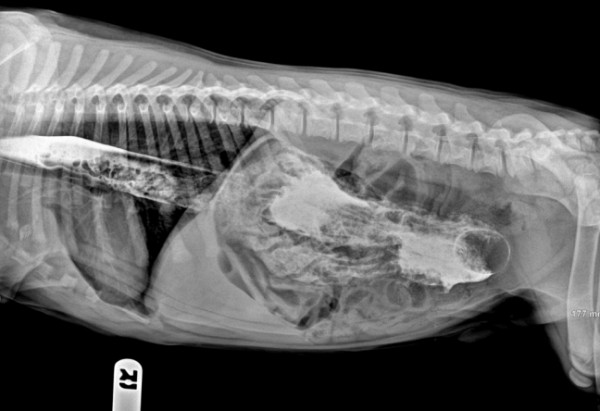

وأظهرت تلك الصور واللقطات صوراً بالأشعة السينية لبطون الحيوانات، أبرزها ابتلاع جرو صغير سكيناً طولها 120 سنتيمتراً؛ ما يوازي نحو 30 بوصة.

وأظهرت تلك الصور، التي التُقطت من قِبل مجموعة من الأطباء البيطريين، كيف أن الحيوانات تبتلع أحيانا أشياءً غريبة، مثل ابتلاع كلب آخر ضلع كامل لحيوان، فيما ابتلعت قطة أذرع تحكم "بلاي ستيشن".